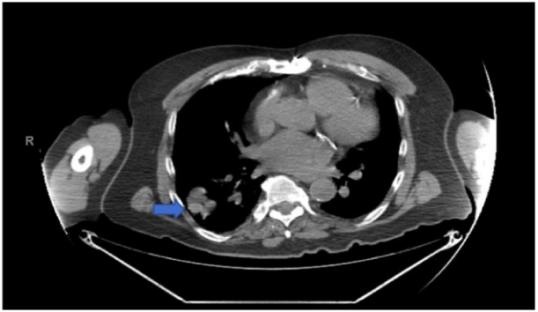

76岁男性患者,无吸烟史,有阻塞性睡眠呼吸暂停病史,接受选择性左膝全关节置换术。第二天,患者出现了非进展性连续咳嗽。胸部X线提示右肺结节状不规则阴影(图1)。胸部电脑断层扫描(CT)显示右下叶上段有一个3.2x2x4.3厘米的肿块和一个1.6厘米的颈下淋巴结(图2)。正电子发射断层扫描(PET)显示早期和延迟成像时右下叶都有活动(图3)。在身体其他部位未发现异常病灶。右下叶病变活检显示一个侵袭性,低分化,恶性黑色素瘤(图4)。患者出院后接受肺部药物治疗,两个月后接受选择性支气管镜下右下叶楔形切除术,进行淋巴结清扫和活检,并取呼吸道多处组织进行活检。最终,患者被诊断为3.7厘米的恶性黑色素瘤,边缘阴性,没有转移的迹象;因此,未发现化疗及放疗的指征。连续重复的CXR和CT扫描显示术后变化稳定,无复发迹象。到目前为止,在诊断后3年零8个月,病人继续每6个月随访一次,没有复发的记录。

图2. 胸部CT。箭头:右下叶上段3.2x2x4.3厘米的肿块。